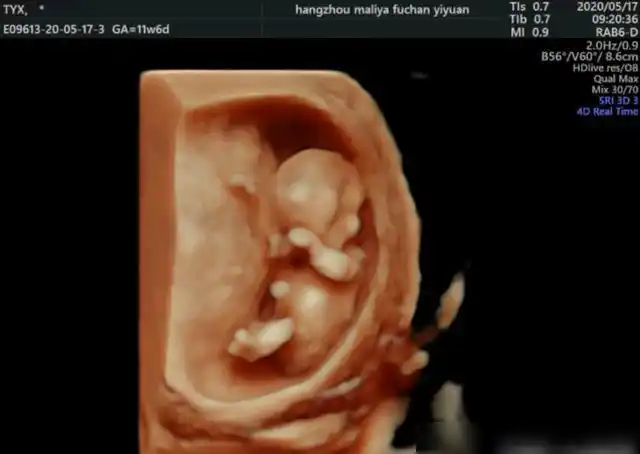

关于nt检查,孕妈妈孕13周前一定要看|羊水|胎儿|b超|穿刺|孕妇_网易